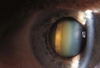

Que fase da catarata ?

Caracterize a fase madura da catarata

A

Cristalino totalmente opaco, não é possível ver retina e nem o reflexo pupilar. Pupila está esbranquiçada (leucocoria).